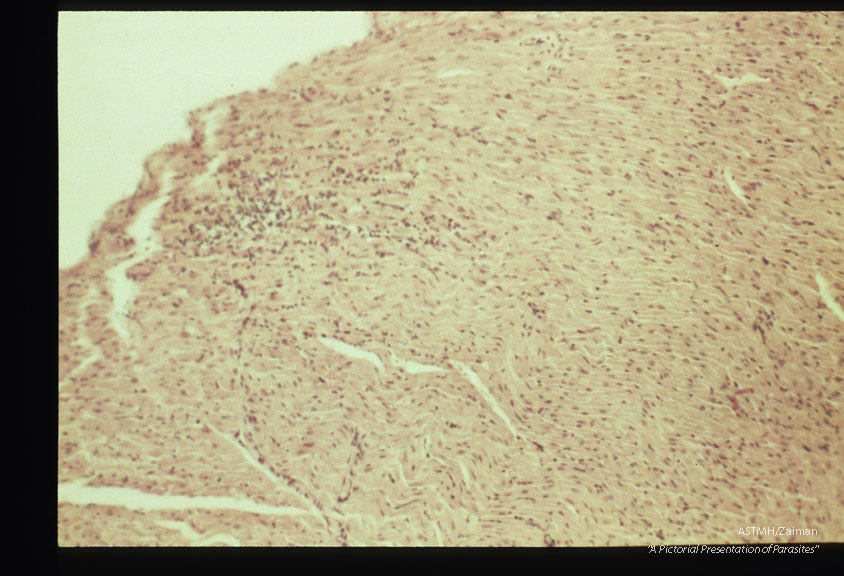

Focal myocardial lesions at low and high powers. Experimental trichinous myocarditis in rats.

Description: Focal myocardial lesions at low and high powers. Experimental trichinous myocarditis in rats.